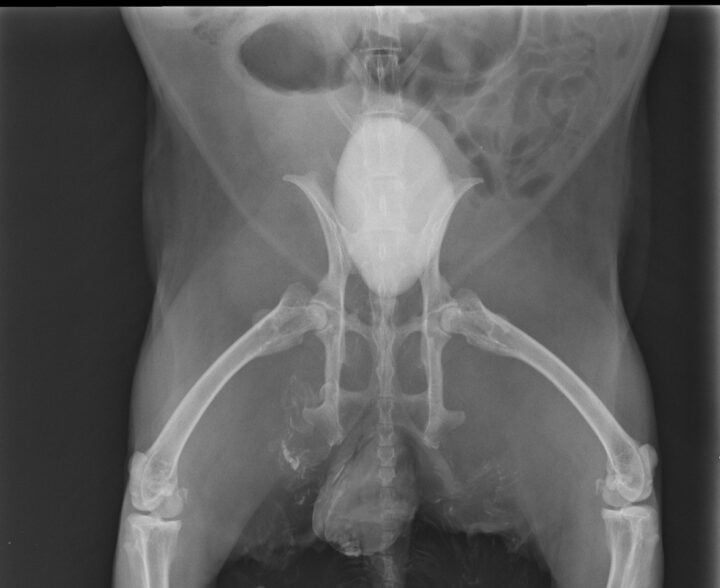

Common symptoms of urolithiasis in guinea pigs include stranguria, haematuria and signs of discomfort or pain when urinating, such as vocalisation. Diagnosis of urolithiasis in guinea pigs is similar to diagnosis in rabbits, using physical examination, urinalysis and imaging techniques, such as radiographs or ultrasound. Radiographs will often reveal the presence of stones (Figure 4), though small stones may be missed if they are not radiopaque. Ultrasound can be particularly useful for detecting smaller stones or those located in the kidneys or ureters.

Diagnosis is achieved through radiographs, ultrasound and urinalysis in the same way as rabbit and guinea pig patients. Radiographs will typically reveal the presence of radiopaque stones, while ultrasound can help identify smaller or less visible stones. Urinalysis may show the presence of crystals, bacteria or blood. Surgical cystocentesis to remove the stone is often the treatment of choice. Following removal of the stone, submitting the sample for culture and composition analysis may prove useful in treatment. Prevention of further urolithiasis formation involves dietary modification by transitioning the patient to an animal-protein-based diet and increasing water intake.